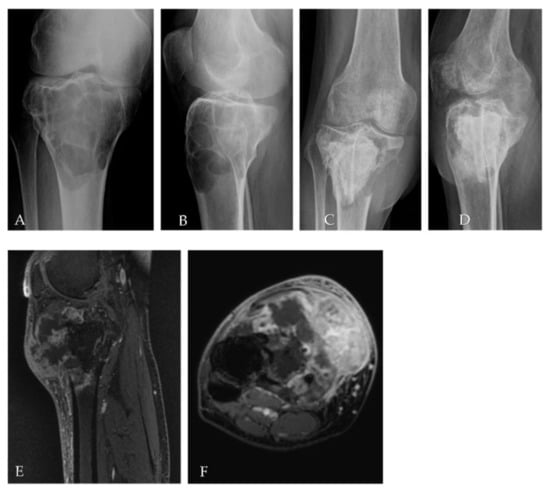

2.3. Patient 3

| Pt 3 | 20 | F | 0 | 10 September | Left femur | Resection of the femoral head, curettage and bone grafts | 11 March | Biopsy | 11 June Biopsy: high-grade osteosarcoma G3 with aberrant expression of beta-HCG | ISG/OS-1 | PD | - | D 11 November | 9 | 14 | 5 |